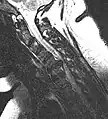

- Magnetic resonance imaging is the gold standard study for confirming a suspected LDH. With a diagnostic accuracy of 97%, it is the most sensitive study to visualize a herniated disc due to its significant ability in soft tissue visualization. MRI also has higher inter-observer reliability than other imaging modalities. It suggests disc herniation when it shows an increased T2-weighted signal at the posterior 10% of the disc. Degenerative disc diseases have shown a correlation with Modic type 1 changes. When evaluating for postoperative lumbar radiculopathies, the recommendation is that the MRI is performed with contrast unless otherwise contraindicated. MRI is more effective than CT in distinguishing inflammatory, malignant, or inflammatory etiologies of LDH. It is indicated relatively early in the course of evaluation (<8 weeks) when the patient presents with relative indications like significant pain, neurological motor deficits, and cauda equina syndrome. Diffusion tensor imaging is a type of MRI sequence used for detecting microstructural changes in the nerve root. It may be beneficial in understanding the changes that occur after herniated lumbar disc compresses a nerve root, and might help in differentiating the patients that need surgical intervention. In patients with a high suspicion of radiculopathy due to lumbar disc herniation, yet the MRI is equivocal or negative, nerve conduction studies are indicated.[44] T2-weighted images allow for clear visualization of protruded disc material in the spinal canal.

MRI scan of cervical disc herniation between C5 and C6 vertebrae

MRI scan of cervical disc herniation between C6 and C7 vertebrae